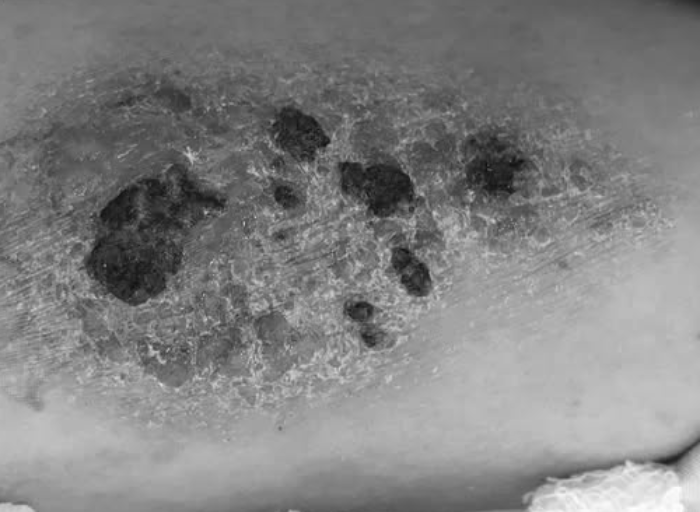

Hình ảnh tổn thương biến chứng do xăm. Ảnh: BVCC.

Các bác sĩ chẩn đoán u mềm lây lan do nhiễm virus sau xăm mình, điều trị bằng cách nạo lấy thương tổn trên da.